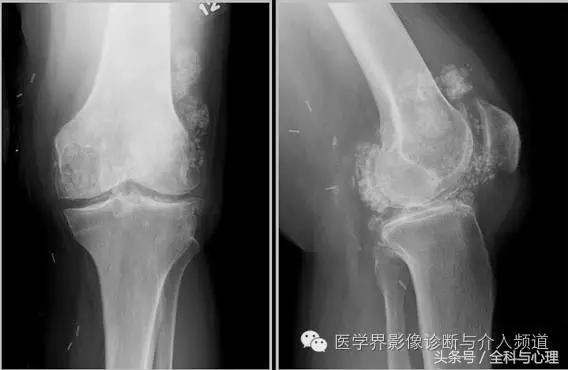

五、滑膜软骨瘤病

1°少见,病灶数量多,大小均匀,相邻关节正常。

2°多见,病灶数量少,大小不一,多伴有退行性骨关节病。

软组织钙化与骨化,软组织钙化和骨质增生 滑膜骨软骨瘤病 1°

软组织钙化与骨化,软组织钙化和骨质增生 滑膜骨软骨瘤病 2°

软组织钙化与骨化,软组织钙化和骨质增生 滑膜骨软骨瘤病